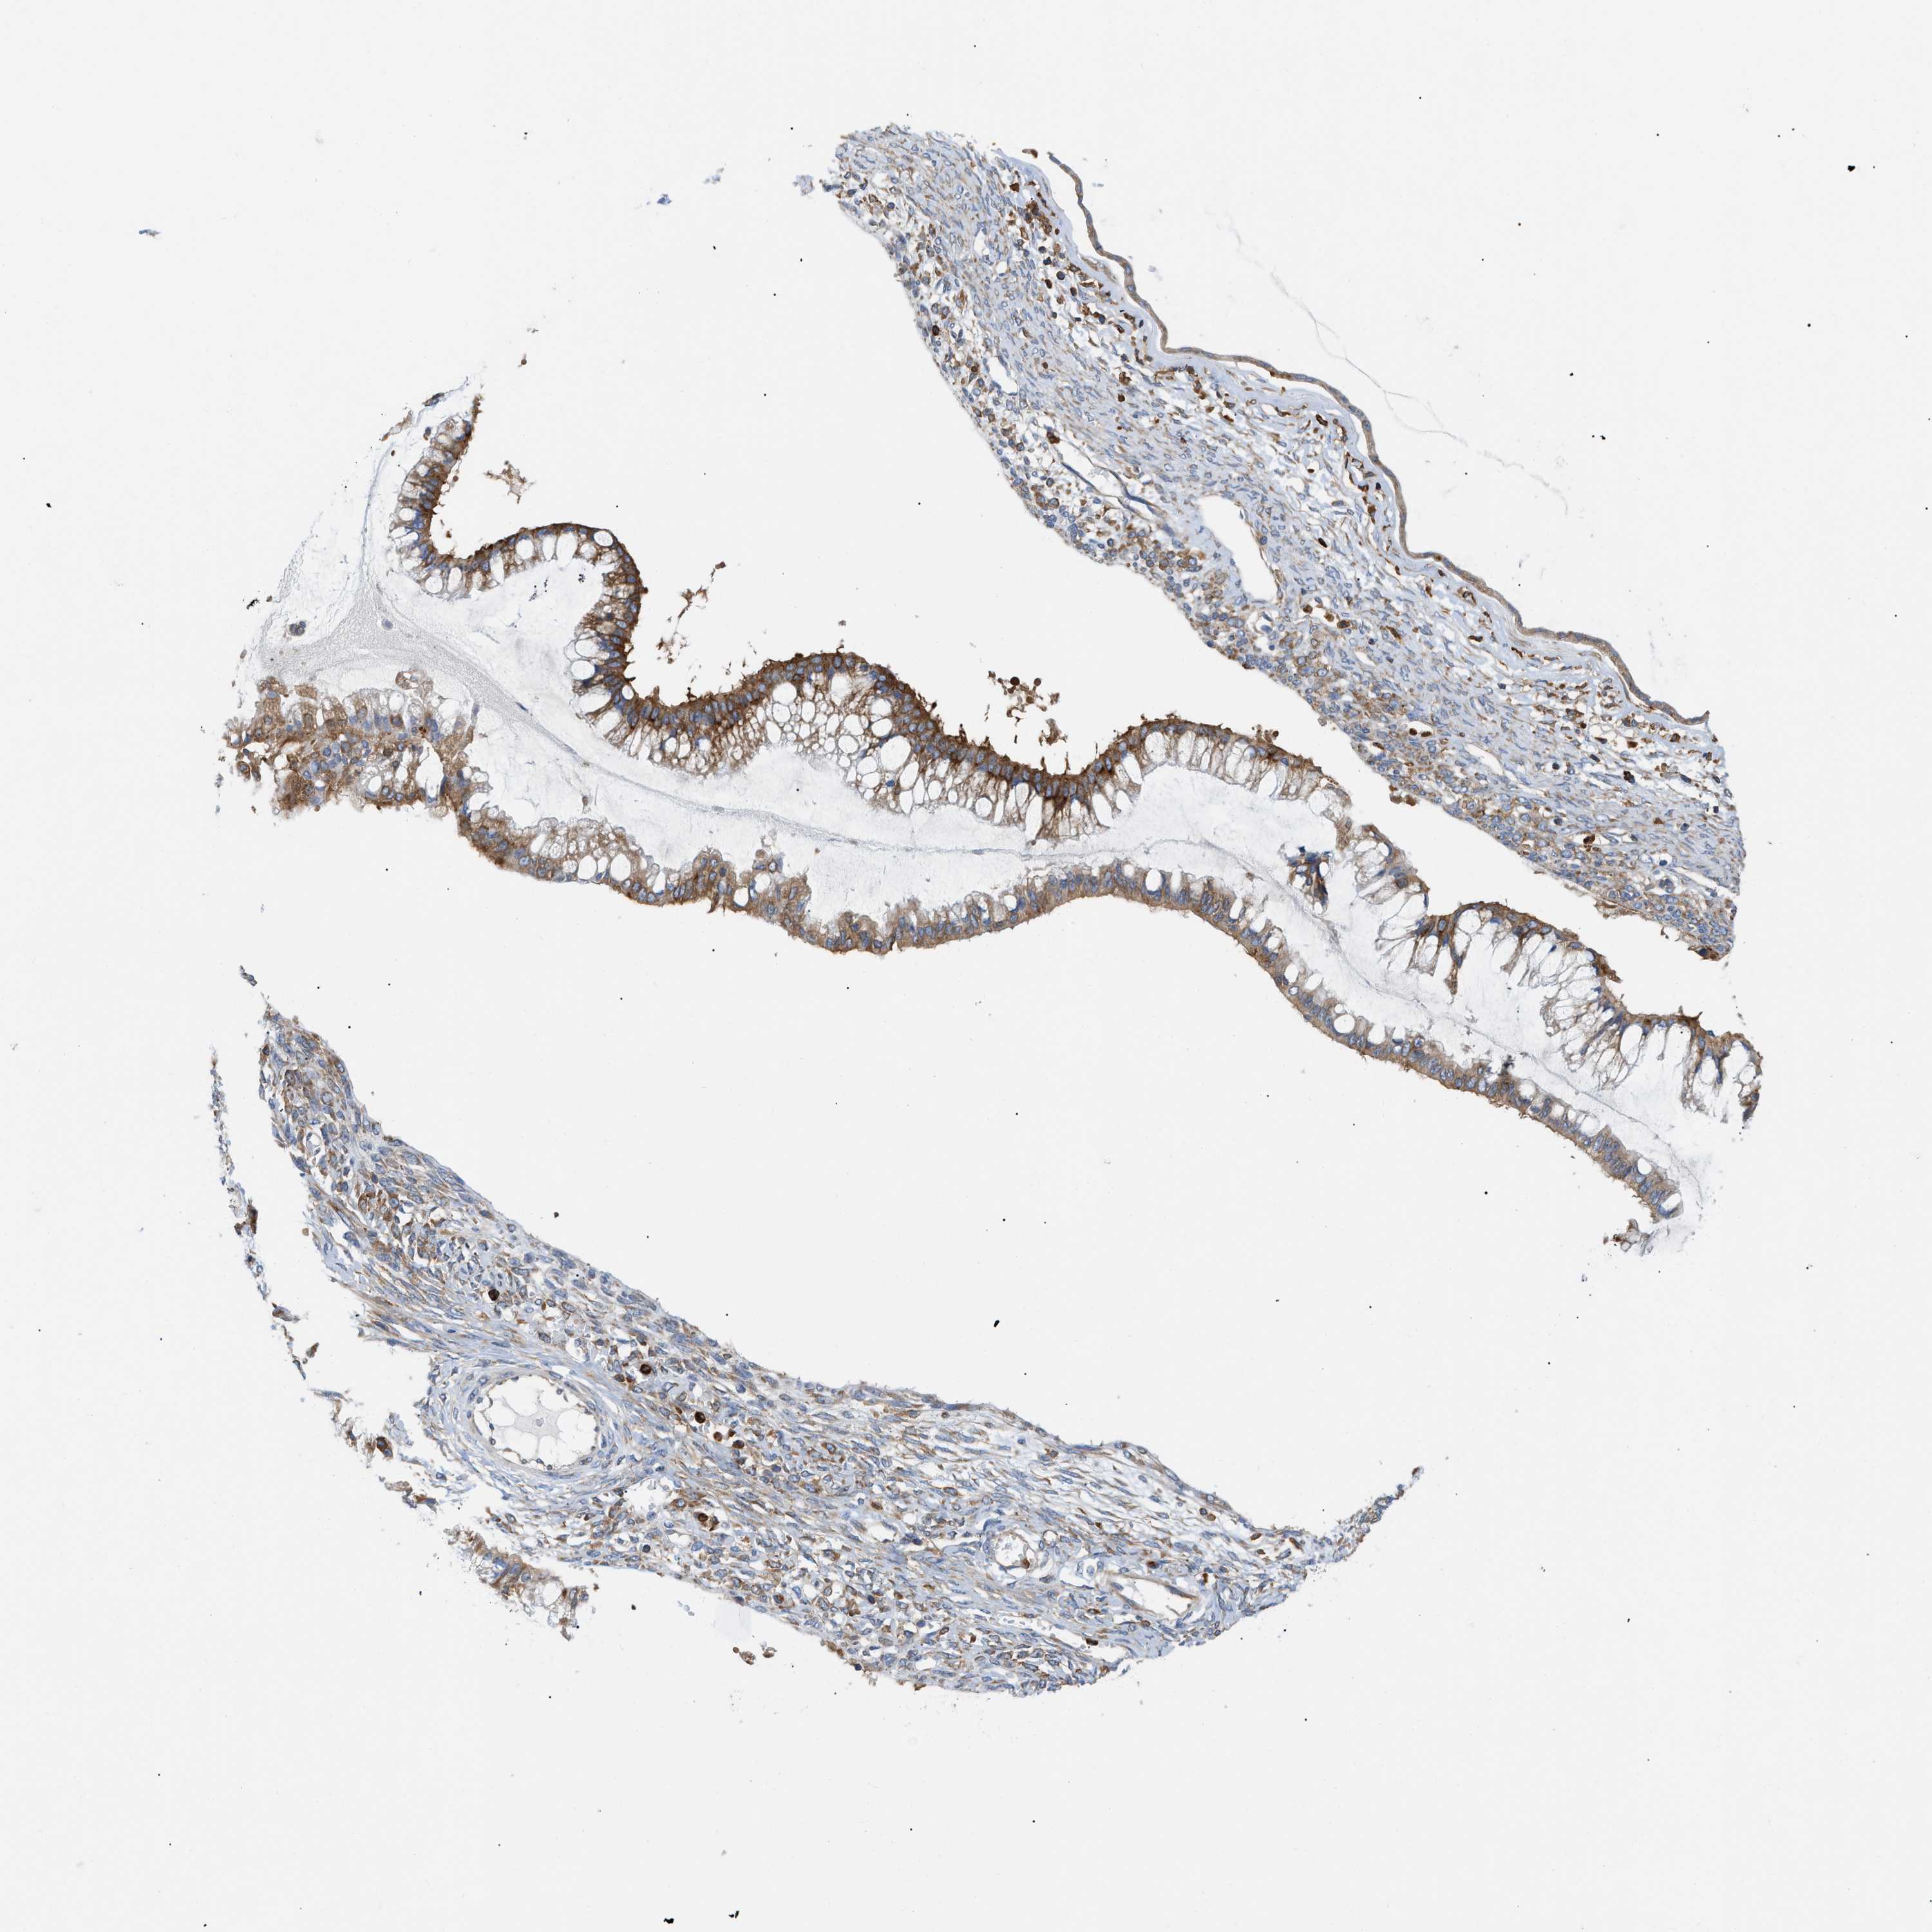

OVARIAN CANCER - Protein expressioni

A mouse-over function shows sample information and annotation data. Click on an image to view it in a full screen mode. Samples can be filtered based on level of antibody staining by selecting one or several of the following categories: high, medium, low and not detected. The assay and annotation is described here.

Note that samples used for immunohistochemistry by the Human Protein Atlas do not correspond to samples in the TCGA dataset.

Antibody stainingi

Antibody staining in the annotated cell types in the current human tissue is reported as not detected, low, medium, or high, based on conventional immunohistochemistry profiling in selected tissues. This score is based on the combination of the staining intensity and fraction of stained cells.

Each image is clickable and will lead to virtual microscopy that enables deeper exploration of all samples and also displays staining intensity scores, fraction scores and subcellular localization as well as patient and tissue information for each sample.

Antibody HPA016471

Staining

High

Medium

Low

Not detected

Intensity

Strong

Moderate

Weak

Negative

Quantity

>75%

75%-25%

<25%

None

Location

Nuclear

Cytoplasmic/membranous

Cytoplasmic/membranous,nuclear

Cystadenocarcinoma, serous, NOS

Carcinoma, endometroid

Cystadenocarcinoma, mucinous, NOS

Carcinoma, NOS